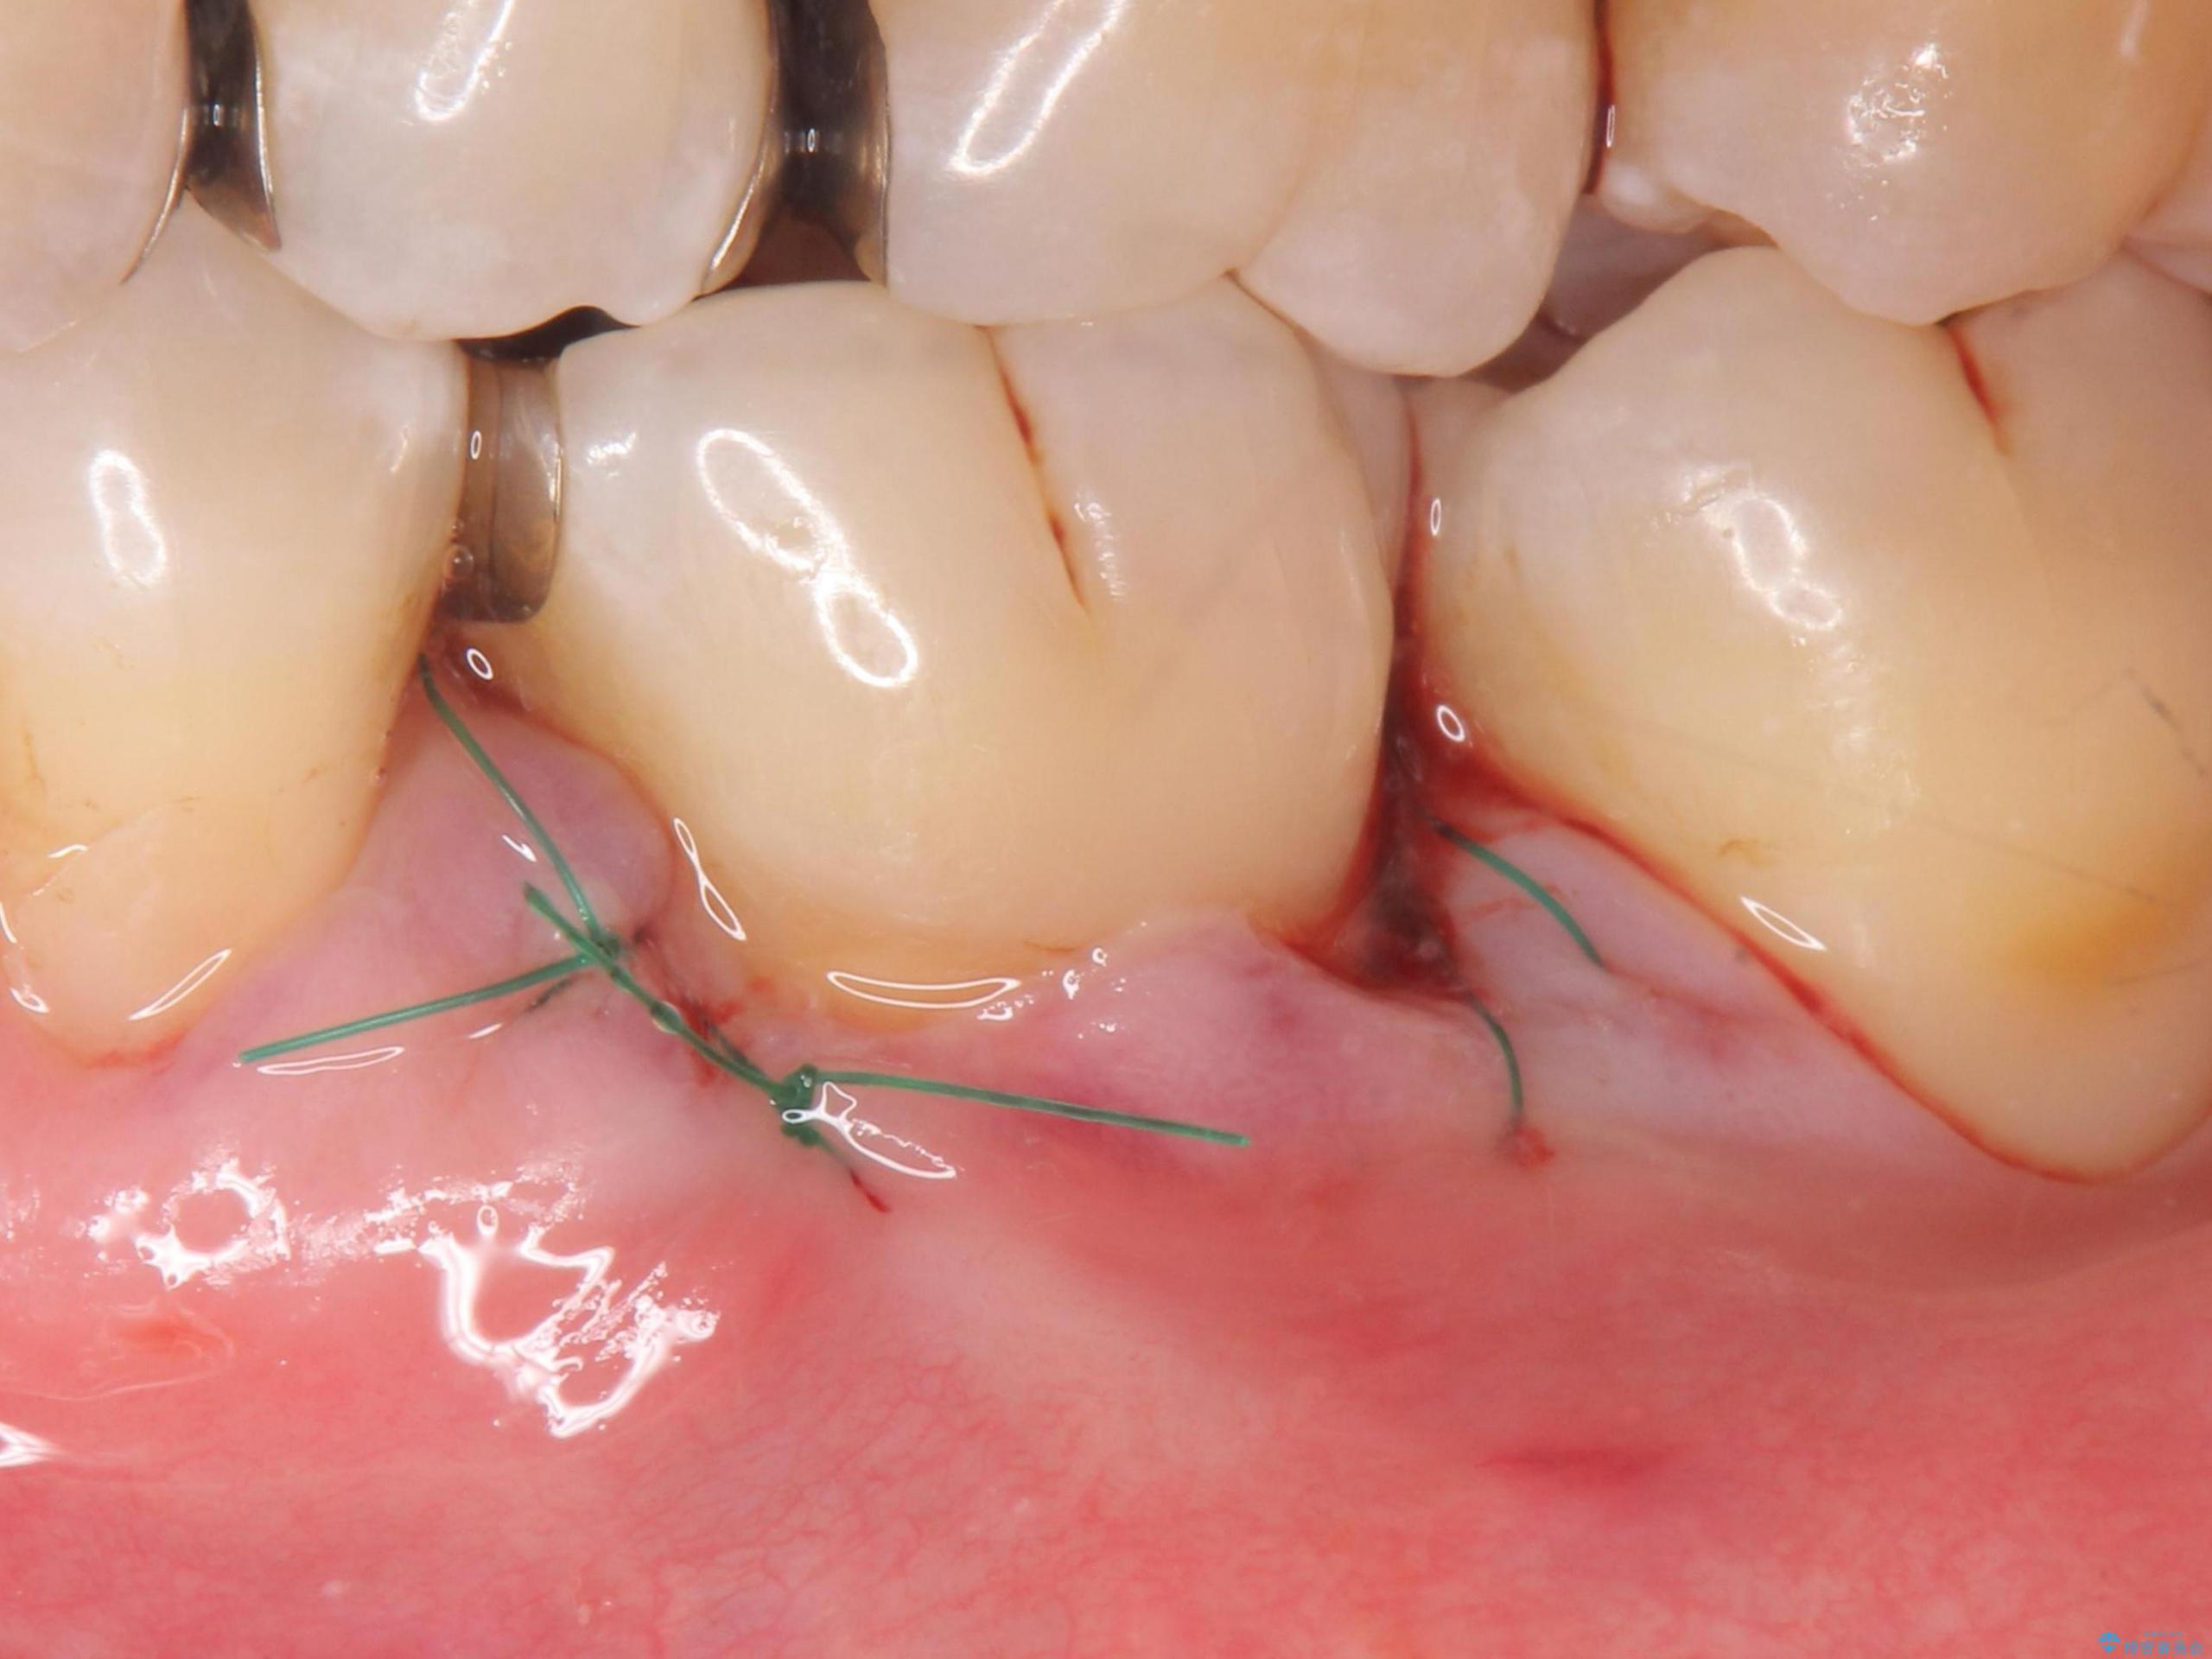

退縮した歯茎に対して移植をすることで、しみる場所を覆う計画です。

歯根の分岐部よりも根尖側の頬側面が露出している状態でしたが、露出部位を分岐部までに抑えることができました。

しみる症状も改善され、大変喜んでいただけました。

術後は歯肉が下がらないよう経過を追っていきます。